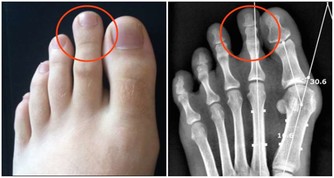

值得注意的是,膝蓋痛有可能是缺鈣、涼風寒濕痺證、骨質增生、受涼受風受濕、肝腎虛弱等所引起的。隨著年齡的增長,站立或者走路久了,膝關節都可能會發生退性行病變。初期,起病緩慢者膝關節疼痛不嚴重,可持續性隱痛,氣溫降低時疼痛加重,與氣候變化有關。

晨起後開始活動,長時間行走,劇烈運動或久坐起立開始走時膝關節疼痛僵硬,稍活動後好轉,上、下樓困難,下樓時膝關節發軟,易摔倒。蹲起時疼痛,僵硬,嚴重時,關節酸痛脹痛,跛行,關節功能受限,以下蹲最為明顯,伸屈活動有彈響聲,部分患者可見關節積液,局部有明顯腫脹、壓痛現象,合併風濕病者關節紅腫、畸形。